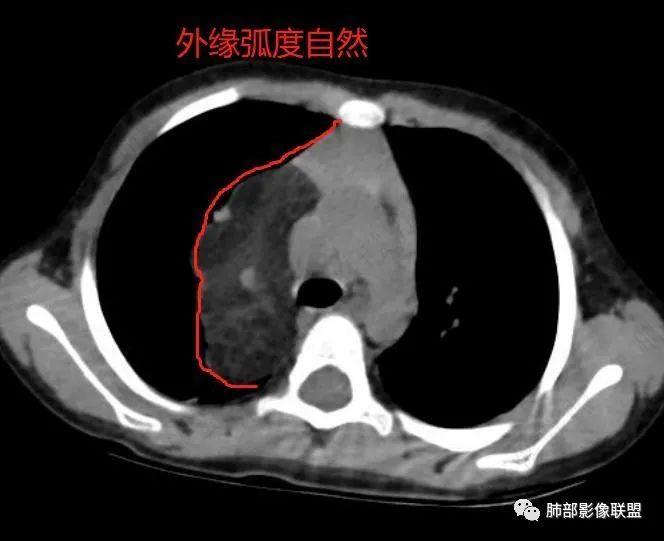

病灶属于交界区,主体位于肺内,占位效应明显,前方突入胸壁,胸腺受压变形,胸膜显示欠清楚;病灶包绕上叶肺动脉;似乎有体动脉供血。符合肺内的点:包绕上叶肺动脉分支;符合纵隔的点:前方似乎突入胸壁,与胸腺关系比较密切,但是与上腔静脉的关系提示病灶不支持纵隔来源,前纵隔的常规会将上腔静脉受压后移、外移,这是不符合的。

1.右上肺-纵隔交界区巨块影,主体位于右肺一侧,紧贴胸腺、头臂干、右锁骨下动脉、上腔静脉、奇静脉等,不能分离,但病灶整体边界清楚。注意上述相邻腔静脉等结构未见受压变形,纵隔亦未见明显向左推移,至少提示两点:

2.肺动脉穿行也许是肺内来源最重要支持点!

CT扫描对脂肪类肿瘤常有独到价值。肿块孤立、边界清楚,未见周围浸润,较均匀脂肪样低密度,高度提示为良性!

发生于成人为脂肪瘤表现,婴幼儿自然会想到脂肪母细胞瘤。两者生物学行为并无本质区别。